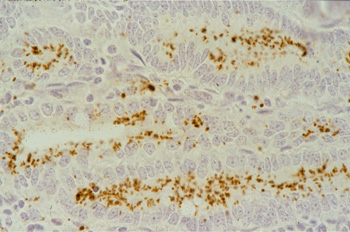

Lawsonia intracellularis cannot be detected by H&E stain. IHC does, reveal a specific reaction of the intracellular organism. The monoclonal antibodies used for Immunohistochemistry can be labeled for a direct in situ immunoperoxidase staining (see pict. 5.2.1 e) or immunofluorescense staining (see pict. 5.2.1 g). This specific reaction is detectable in most of the cases at the luminal aspect of the infected crypt cells, and is occasionally present in macrophages of the lamina propria. In a higher power magnification, there are increased numbers of intraepithelial lymphocytes and a few apoptotic figures recognizable (pict. 5.2.1 f).

Picture 5.2.1 e (by J. Pohlenz)

IHC (immunoperoxidase) of a section of ileum with PIA: dark brown bacteria in enterocytes of crypts and in macrophages of the lamina propria (250x).